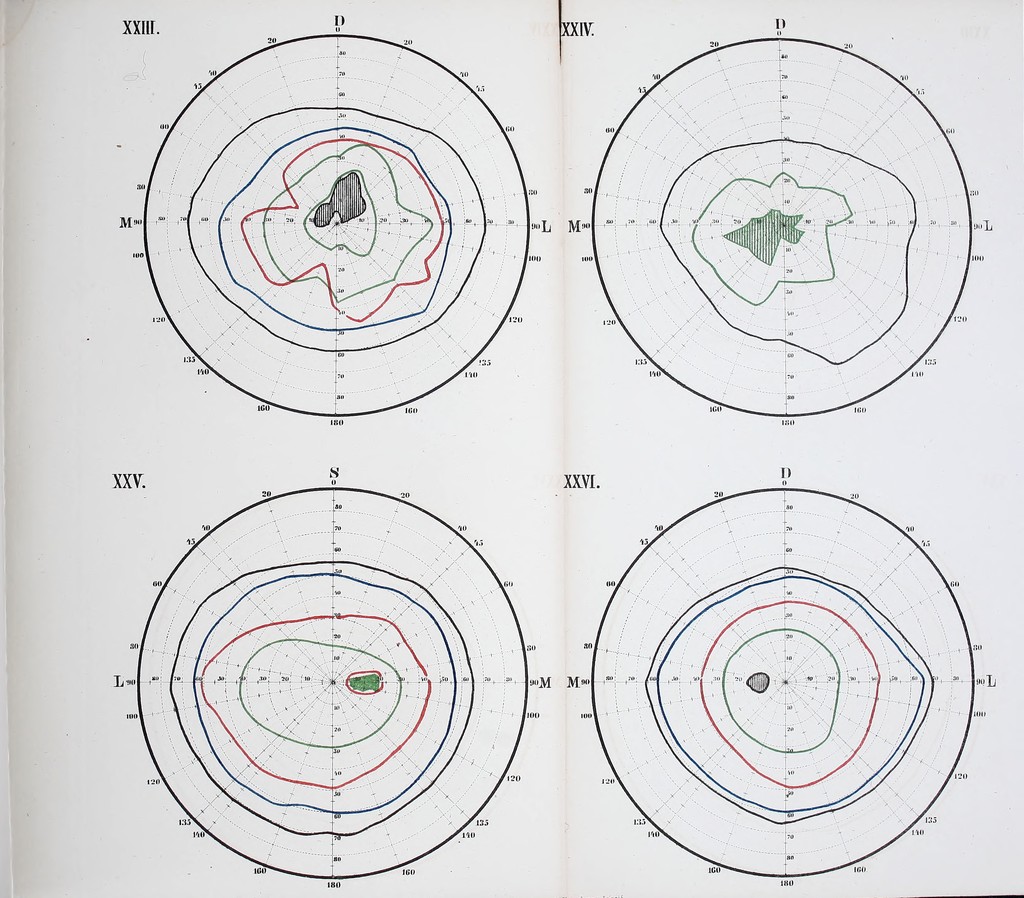

Die Lehre vom Gesichtsfelde und Seinen Anomalien : Eine physiologisch-kinische Studie / von Wilhelm Schoen.

- 1874